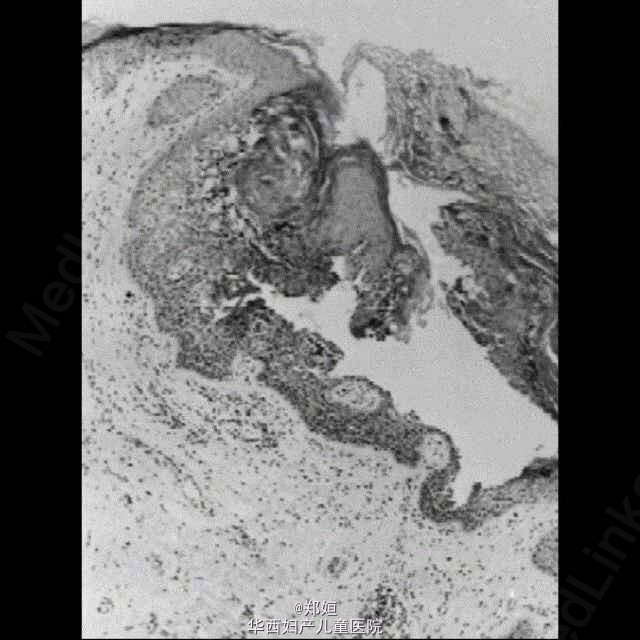

女性外阴丘疹样棘层松解性角化不良

44岁女性,在其左右大阴唇有瘙痒性出疹2年,身体其他部位无类似病灶

活检提示棘层和角化不全的局灶

组织学诊断为疣状角化不良症 行病灶切除术